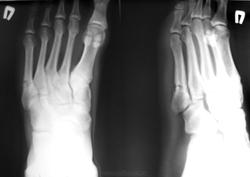

Пол пациента: Мужской пол Тип патологии: Травма Область исследования: Скелетно-мышечная система Методы исследования: Rg Юноша дней 10 назад, на тренировке получил травму стопы. Терпел и наконец пришёл к доктору на приём. ID:17766 Mon, 26/12/2011 - 17:37 #1 DR.RAD Offline Last seen: 11 years 10 months ago Joined: 25.03.2009 - 18:22 Posts: 805 перелом пятой плюсневой кости есть, есть и периостальный формирующийся регенерат. а что смутило? Mon, 26/12/2011 - 18:11 #2 Глазков Игорь А... Offline Last seen: 11 months 1 week ago Joined: 19.12.2008 - 20:41 Posts: 1597 периостального формирующегося регенерата и закрались сомнения. Вначале подумал об осложнении, ввиде периостальной реакции. Прийди к Себе Mon, 26/12/2011 - 19:10 #3 yuriy4508 Offline Last seen: 10 months 1 week ago Joined: 30.09.2011 - 13:08 Posts: 27 перелом плюсневой кости. Скажите, чем вызван интерес к "периостальный формирующийся регенерат" Не встречался с такой формулировкой. Хотелось бы знать подробнее что это такое и каковы последствия? Mon, 26/12/2011 - 20:08 #4 И.Бондаренко Offline Last seen: 2 days 13 hours ago Joined: 13.09.2011 - 22:55 Posts: 9208 Пусть ещё побегает. Tue, 27/12/2011 - 16:08 #5 Александр Викторович Offline Last seen: 8 years 2 months ago Joined: 31.07.2010 - 13:05 Posts: 639 И.Бондаренко wrote: Пусть ещё побегает.

перелом пятой плюсневой кости есть, есть и периостальный формирующийся регенерат. а что смутило?

периостального формирующегося регенерата и закрались сомнения. Вначале подумал об осложнении, ввиде периостальной реакции.